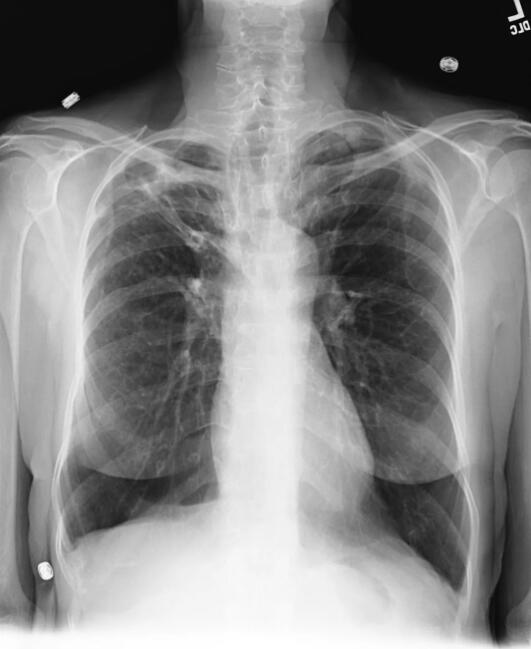

用作診斷依據(jù)的醫(yī)學(xué)成像 CT MRI CR DR